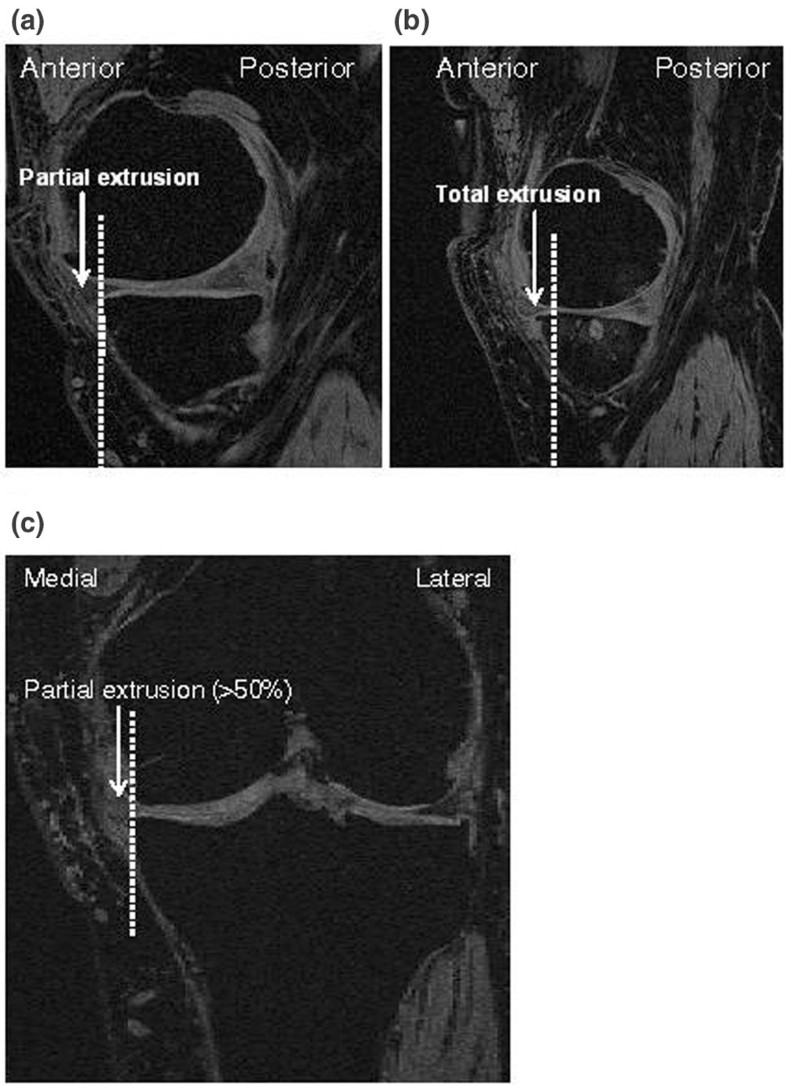

Knee meniscal extrusion in a largely nonosteoarthritic cohort Knee Cartilage Volume the habitual motion path theory: Evidence from cartilage volume reductions in the knee joint after 75. original research | volume 3, issue 4, 100138, december 2023. junfei li, lin bai & jian zhao. Mri is commonly used to evaluate the articular cartilage of. volume 195, issue 3. some studies suggest that high pa levels do. Knee Cartilage Volume.